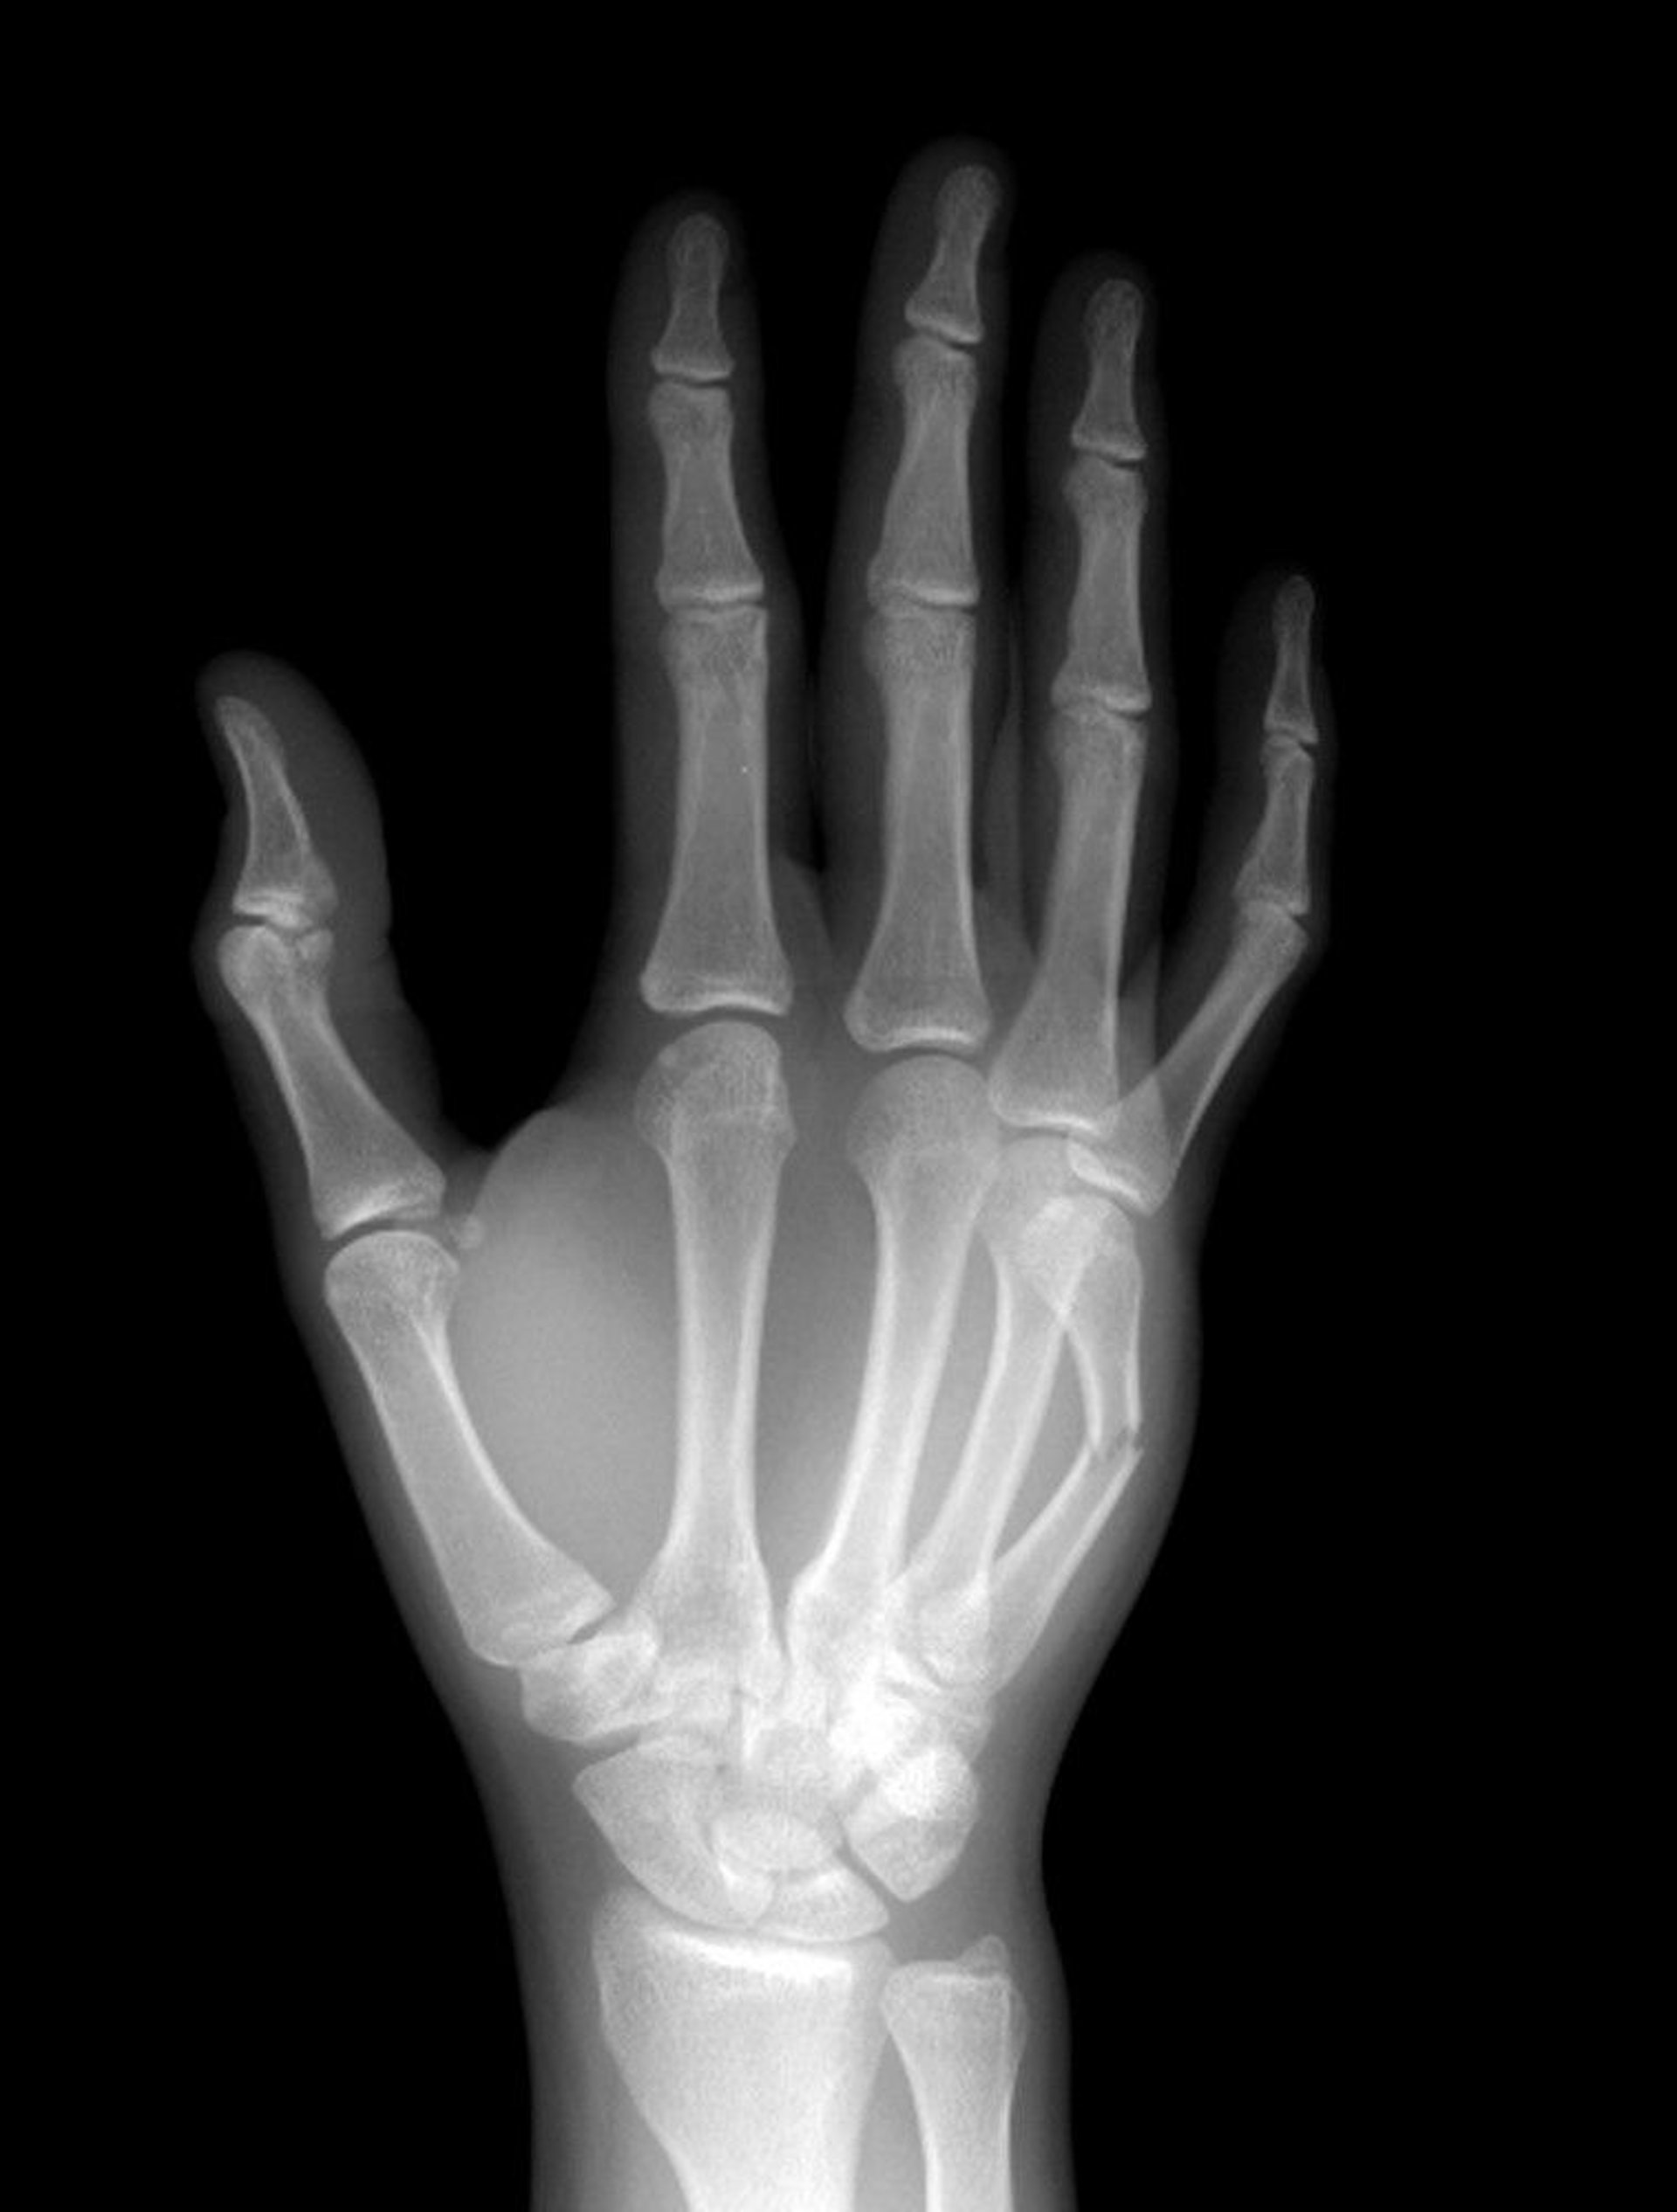

The 5th metacarpal neck bone is fractured midshaft.